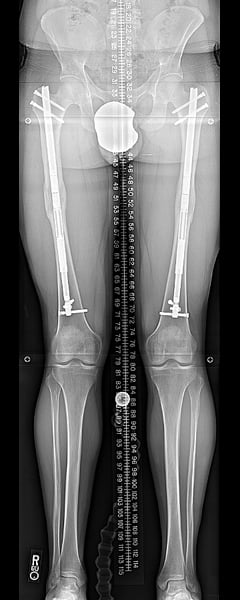

However, in some cases, the lower leg bone (tibia) may be lengthened instead of or in addition to the femur. In such cases, the fibula is also cut and stabilized to the tibia at both ends using screws as sutures, so that it lengthens as well. The fibular lengthening does not require a separate device but is achieved by the tibial lengthening nail.

Tibia at end of consolidation.

Tibias with nails removed.How much taller can stature lengthening surgery make you?

The most common increase in height is three inches (or 8 cm) because that is how long the implanted rods extend. If the procedure is repeated in the lower leg bone (the tibia), another 2 to 3 inches can be obtained, for a total of about 5 to 6 inches of added height.